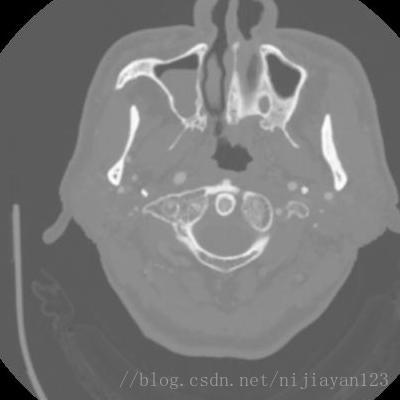

现阶段进行医学图像的深度学习处理的方法,最大的瓶颈就是数据量比较少,导致网络训练不是很理想。由于进行颅内血管的数据量也比较少,所以需要进行一定的数据量的扩充操作。由于颅内的CT图像是3D的数据。在这里,我为了使得进行更好的网络运行,我选择进行了切分操作,获得了2D数据。原来数据大小为242*512*512的,我进行了切割操作变成了400*400*200的数据量。

左边为剪切过的图片。